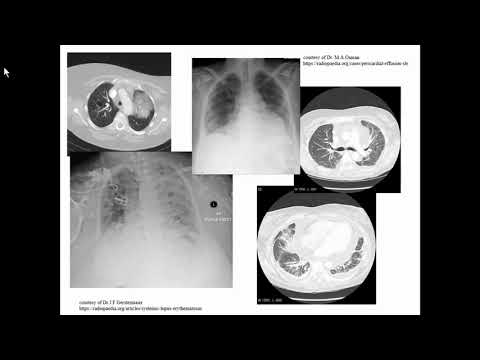

Боярская Ю.B. «Пневмоцистная пневмония vs люпус-пневмонит (как дебют СКВ) у пациента без ВИЧ»